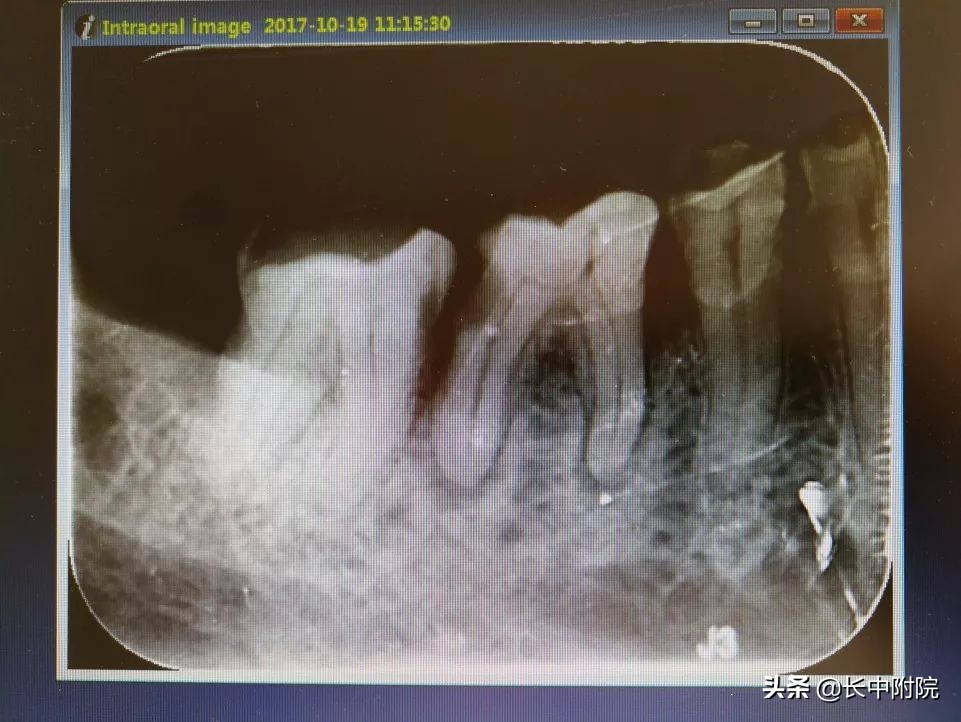

1.术前拍摄X线片

在根管治疗过程中,在根管治疗术前拍X线片,以帮助诊断,了解髓室的位置和根管数目及形态,测量根管工作长度及日后随访和评价疗效提供对比的依据。